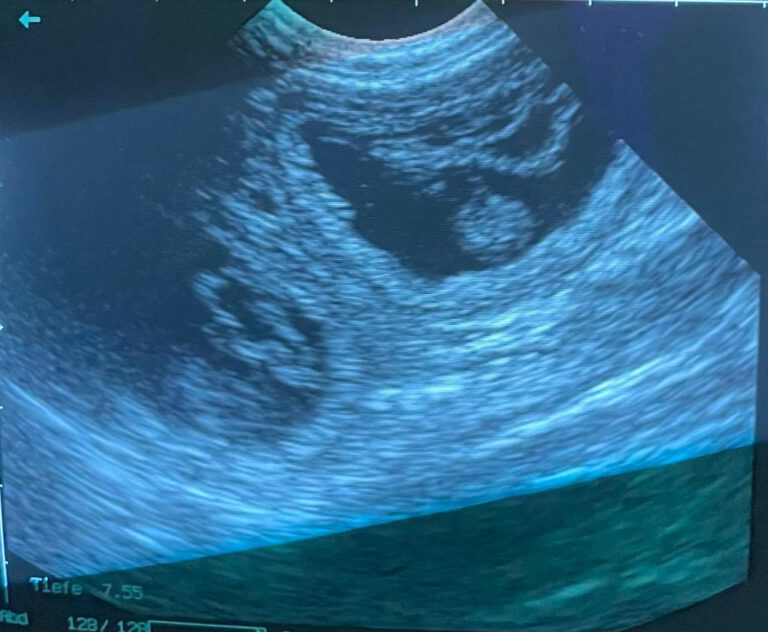

Besuch beim Tierarzt

28.02.2022

Nach der heutigen Ultraschalluntersuchung können wir mit Freude mitteilen, der Deckackt war erfolgreich. Alma ist trächtig.